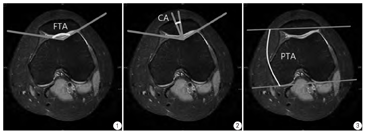

膝关节小角度屈曲位对于评价滑车发育不良更有特异性。目前常用股骨滑车角(femoral trochlear angle,FTA/sulcus angle,SA)反映股骨髁的解剖学特征。FTA是股骨滑车沟最低点分别与股骨内外侧髁最高点的连线形成的夹角(图1),越大提示股骨滑车凹越浅;随着髌骨在膝关节屈曲过程中逐渐进入滑车凹并由浅凹向深凹移动,FTA逐渐减小[18]。文献发现,髌股关节排列异常的患者与对照组的FTA在小角度(即<30° ,亦有文献显示男性0°~20° ,女性0°~10°[19])屈曲时相比伸直时的差异更明显,说明小角度屈曲时通过测量FTA诊断滑车发育不良的特异性更高。

运动医学研究发现,正常人屈膝初期髌骨从起始位置向远端滑移的同时也开始向膝关节内侧移动,屈膝至15°~30°时,髌骨内移逐渐达到最大,然后转向外侧移动,至屈膝40°时,髌骨又回到中位线上[20]。而髌股关节不稳的患者在膝关节屈曲15°~45°时髌骨中心从初始外移位置持续向外侧移动[21,22],因此30°时正常人与患者的差异可能更显著,这种运动轨迹的差异同样体现MR图像上[23]。评估髌骨脱位/半脱位时常用适合角(congruence angle,CA),即股骨滑车沟最低点和髌骨中央脊的连线与FTA的平分线所形成的夹角(图2),此角在平分线的外侧为正值,正值越大说明髌骨越向外移,>16°可以诊断半脱位[24]。多数文献表明,髌股关节不稳的患者与对照组的CA在屈膝<30°时差异较明显[25],且屈曲30°时髌骨半脱位的发现率高于0°及45°[26],因为此时髌骨的运动受滑车凹及伸膝装置的影响尚小,髌骨最不稳定;而屈膝>30°时,伸膝装置紧张度增加、滑车凹骨性突起等因素会减轻髌骨移位,因此轻微的髌骨脱位不能被确切反映出来。

国内外文献发现,在10°~30°时评价髌骨倾斜较为准确。广泛应用于评估髌骨倾斜的参数是髌骨倾斜角(patellar tilt angle,PTA/lateral patellar tilt,LPT)。PTA指的是髌骨内外侧最突出点与股骨髁后缘软骨下骨切线的夹角(图3),此角度为正值时提示髌骨外倾,角度越大提示外倾程度越大,从膝关节伸直位到屈曲30°时PTA逐渐减小。有学者发现,45°时髌股关节不稳患者与正常人十分接近[23],提示在45°时测量PTA对诊断髌骨倾斜几乎没有临床意义。另外,类似BSO,正常人在伸直位且股四头肌紧张时测量的PTA可以达到正常值高限,在伸直位时测得的PTA可能影响临床判断[27]。因此,选择在10°~30°时测量PTA评价髌骨倾斜可能是一个相对合适的妥协[28]。